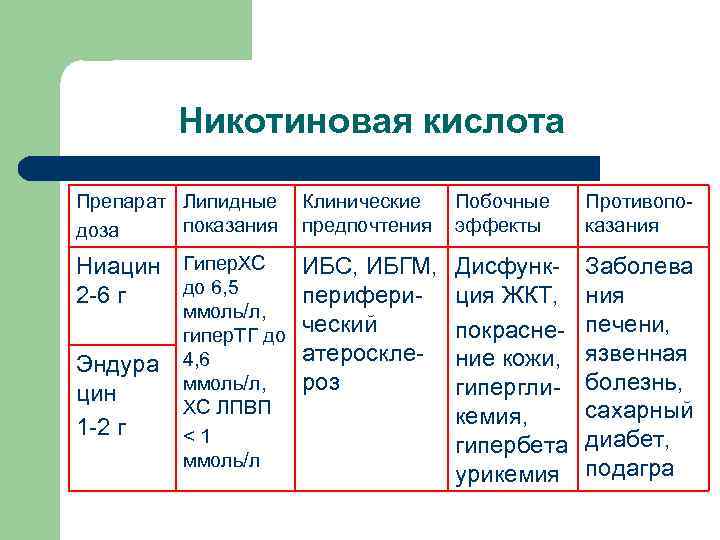

Никотиновая кислота Препарат Липидные показания доза Ниацин Гипер. ХС до 6, 5 2 -6 г Клинические предпочтения ИБС, ИБГМ, перифериммоль/л, ческий гипер. ТГ до атероскле. Эндура 4, 6 роз ммоль/л, цин ХС ЛПВП 1 -2 г <1 ммоль/л Побочные эффекты Противопоказания Дисфункция ЖКТ, покраснение кожи, гипергликемия, гипербета урикемия Заболева ния печени, язвенная болезнь, сахарный диабет, подагра